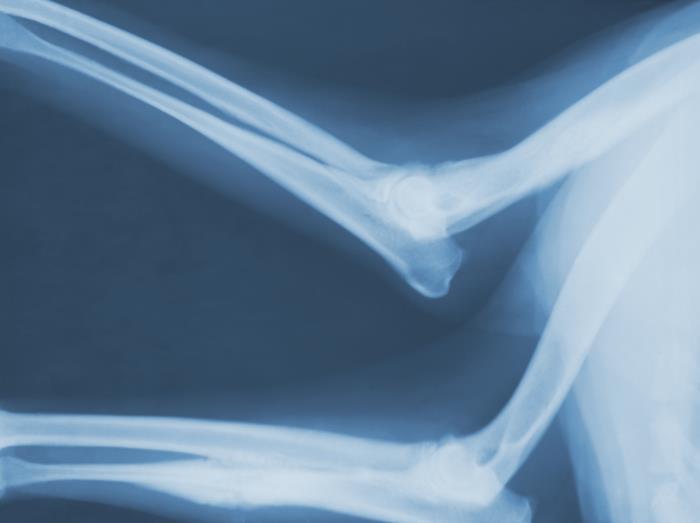

This radiograph depicts a left lateral view of a patient’s elbow joints, highlighting the pathologic changes due to a case of coccidioidomycosis, caused by a fungal organism of the genus, Coccidioides. Note how the ensuing disease process had affected the left ulna at its midshaft region, and the right humerus in its middle and distal third.